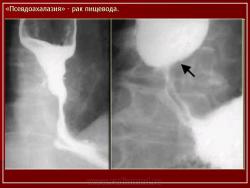

ПС. Пищевод. Набор изображений № 2. Новообразования пищевода. Варикозно расширенные вены пищевода. +

Пищевод.  Набор изображений № 2.